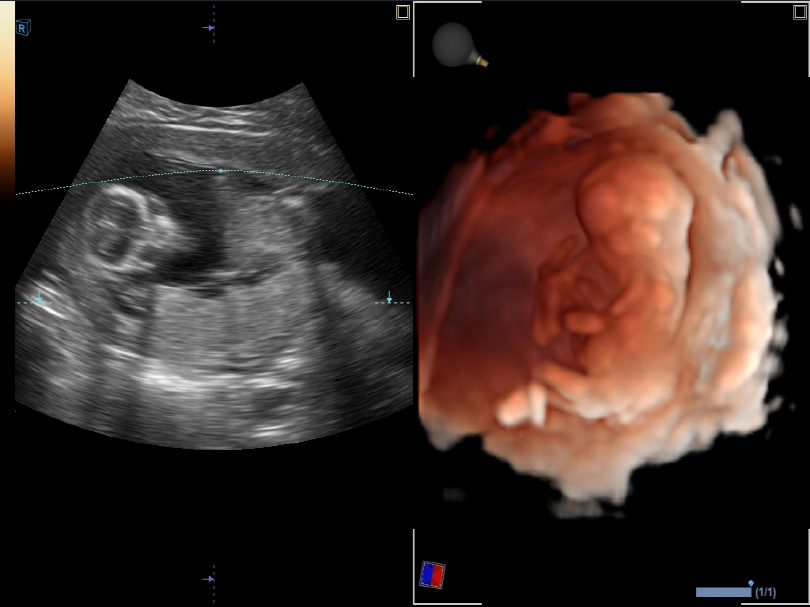

VE3-10H

High density volume endocavity transducer (3-10MHz)

Application:

GYN, OB, Urology, EM